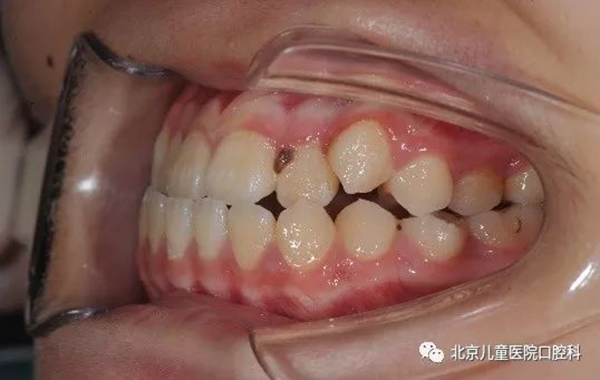

3、牙列整体远移,见于轻度牙列不齐,轻度牙齿前突,或轻度地包天的病例。

治疗前